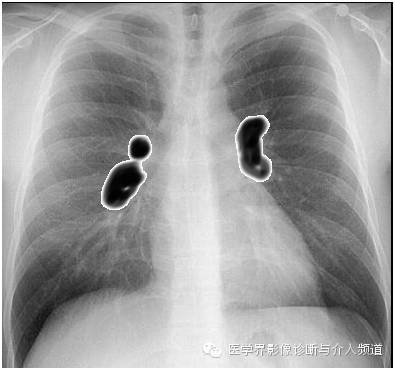

再来一张帅爆了的模式图:

1、胸内淋巴结肿大是结节病最常见的表现,双侧肺门及右侧气管旁淋巴结肿大是最常见的特征性表现。

2、肺门淋巴结肿大通常呈双侧对称性分布。